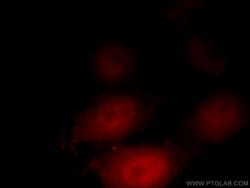

Supportive validation

- Submitted by

- Proteintech Group (provider)

- Main image

- Experimental details

- Immunofluorescent analysis of HepG2 cells, using NR3C1 antibody 24050-1-AP at 1:50 dilution and Rhodamine-labeled goat anti-rabbit IgG (red).

- Sample type

- cell line